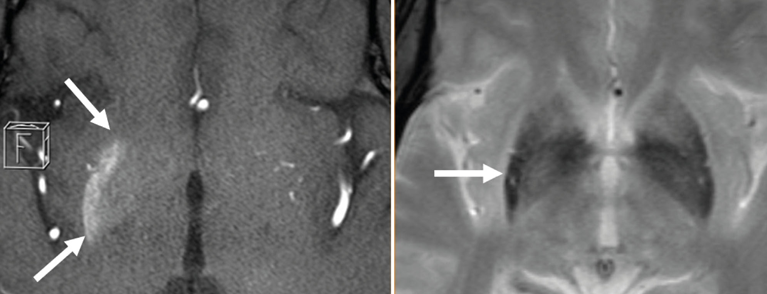

Hemichorea-Hemiballismus im Rahmen der nicht-ketotischen Hyperglykämie

Einleitung: Hyperkinesien durch Funktionsstörungen der Stammganglien können durch eine ­Reihe von vorwiegend vaskulären und (para)in­fektiösen sowie endokrinen Erkrankungen hervorgerufen werden. Nachfolgend berichten wir über den seltenen Fall eines Patienten mit Diabetes mellitus Typ 2, bei dem die Bildgebung wegweisend war für die Diagnosestellung eines schwersten Hemichorea-Hemiballismus-Syndroms im Rahmen einer nicht-ketotischen Hyperglykämie.